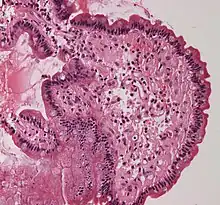

In the clinical setting, amyloid diseases are typically identified by a change in the spectroscopic properties of planar aromatic dyes such as thioflavin T, congo red or NIAD-4.[73] In general, this is attributed to the environmental change, as these dyes intercalate between β-strands to confine their structure.[74]

Congo Red positivity remains the gold standard for diagnosis of amyloidosis. In general, binding of Congo Red to amyloid plaques produces a typical apple-green birefringence when viewed under cross-polarized light. Recently, significant enhancement of fluorescence quantum yield of NIAD-4 was exploited to super-resolution fluorescence imaging of amyloid fibrils[75] and oligomers.[76] To avoid nonspecific staining, other histology stains, such as the hematoxylin and eosin stain, are used to quench the dyes' activity in other places such as the nucleus, where the dye might bind. Modern antibody technology and immunohistochemistry has made specific staining easier, but often this can cause trouble because epitopes can be concealed in the amyloid fold; in general, an amyloid protein structure is a different conformation from the one that the antibody recognizes.